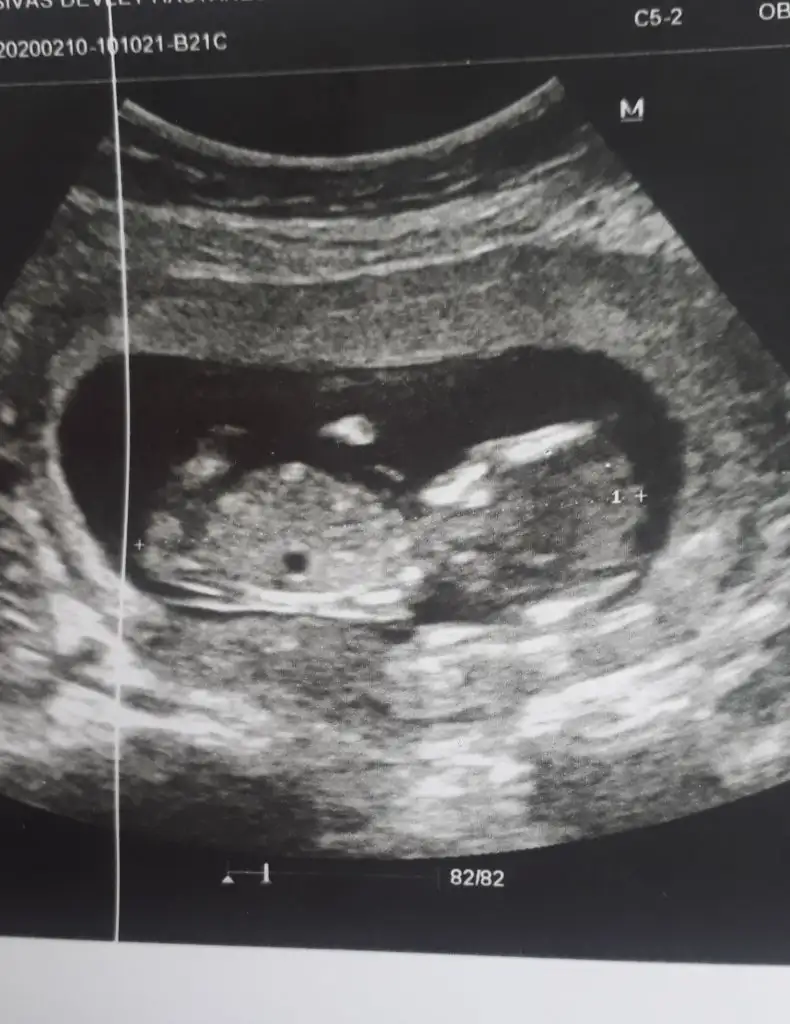

Canım bende merak ediyorum seni benimde 3 oglum var bu 4. Ins hayırlısıyla bi kızımız olur